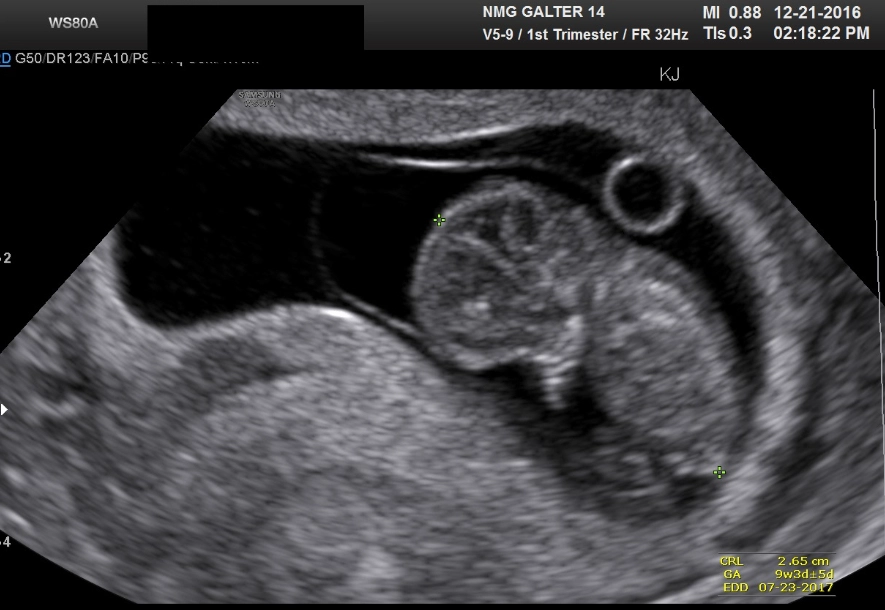

The big milestone: Your first-trimester screening (often between weeks 11-13) might include a nuchal translucency ultrasound and blood tests. This checks for certain chromosomal conditions. It can be an anxious wait for results, but also incredibly special—you might get to see your baby bouncing around!